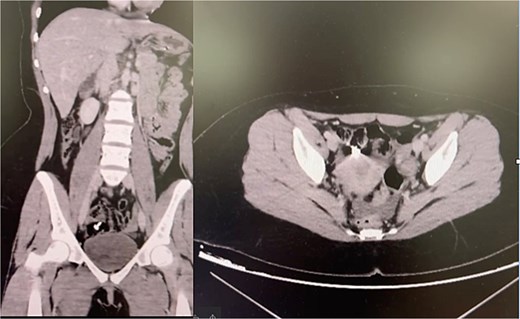

Case 3—Metal nail in the colon

A 22-year-old woman with suspected mood dysregulation ingested a 4-cm nail. Abdominal radiographs revealed a metallic foreign body in the right lower quadrant; CT confirmed its location in the cecum (Fig. 3). She remained asymptomatic and was managed conservatively with a high-fiber diet and serial abdominal imaging. The nail passed uneventfully within 72 h.

Teaching point: Not all sharp objects mandate immediate surgery. Small, linear metallic items may pass spontaneously under close monitoring, but vigilance is essential to detect perforation or obstruction [7–9].